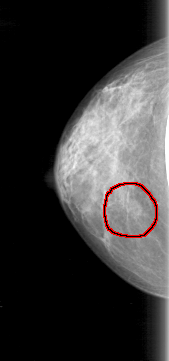

D_4085_1.RIGHT_CC

RIGHT_CC LINES 4681 PIXELS_PER_LINE 2191 BITS_PER_PIXEL 12 RESOLUTION 43.5 OVERLAY

FILE: D_4085_1.RIGHT_CC.OVERLAY

TOTAL_ABNORMALITIES 1

ABNORMALITY 1

LESION_TYPE MASS SHAPE OVAL MARGINS OBSCURED

ASSESSMENT 0

SUBTLETY 3

PATHOLOGY BENIGN

TOTAL_OUTLINES 1

BOUNDARY